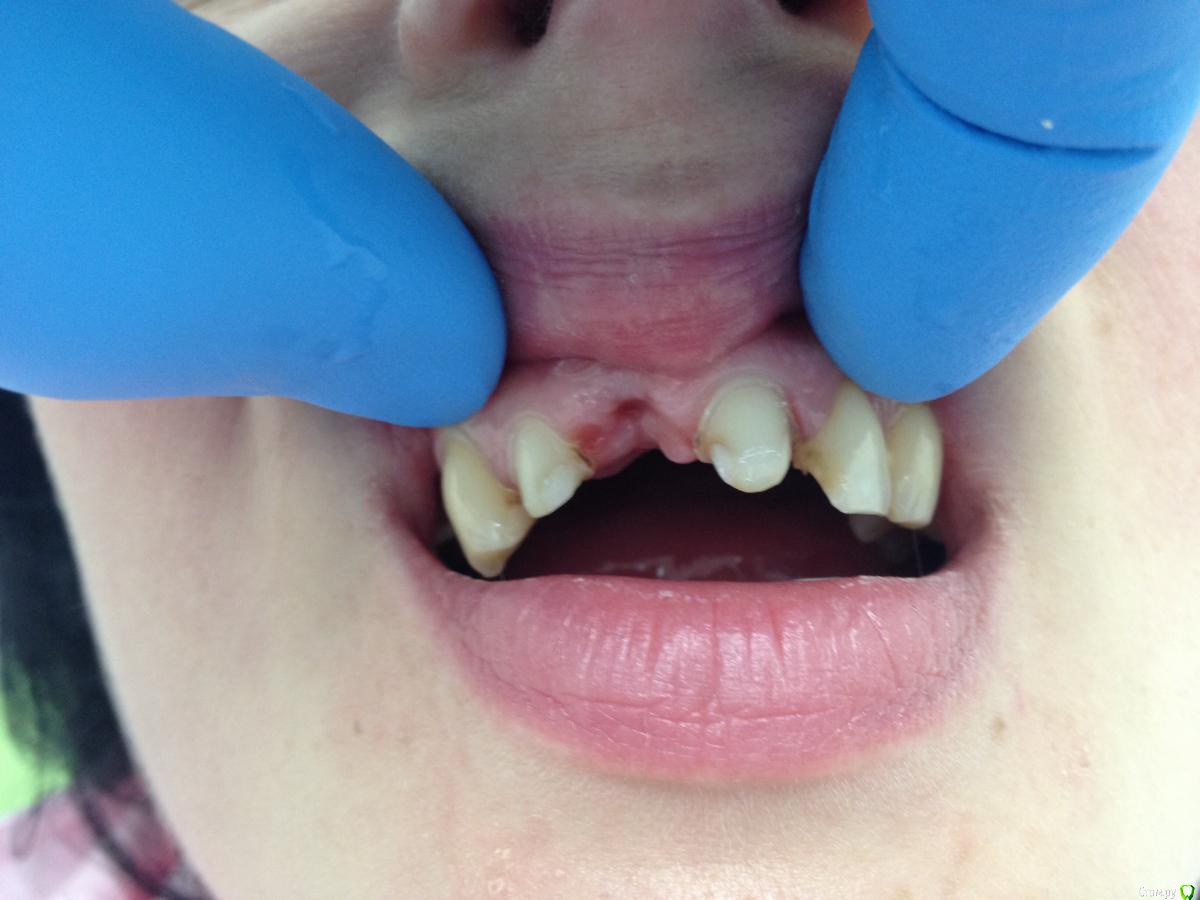

DoctorT Опубликовано 2 апреля, 2015 Поделиться Опубликовано 2 апреля, 2015 (изменено) Решил побаловаться и сотворить овоид))) Изменено 2 апреля, 2015 пользователем DoctorT 1 Ссылка на комментарий

Dr.Zoom Опубликовано 2 апреля, 2015 Поделиться Опубликовано 2 апреля, 2015 на 21 кариес не смущает? Ссылка на комментарий

DoctorT Опубликовано 2 апреля, 2015 Поделиться Опубликовано 2 апреля, 2015 (изменено) на 21 кариес не смущает? абсолютно нет Изменено 2 апреля, 2015 пользователем DoctorT Ссылка на комментарий

molchanoff Опубликовано 2 апреля, 2015 Поделиться Опубликовано 2 апреля, 2015 Решил побаловаться и сотворить овоид)))себя побаловать?в позиции 11 не овойд под мост, а имплант нужен.а то вы соединили жесткой конструкцией кости в.ч. и радуетесь. Ссылка на комментарий

DoctorT Опубликовано 2 апреля, 2015 Поделиться Опубликовано 2 апреля, 2015 (изменено) Т.е. мост есть противопоказан? Вы считаете, что зубы в кости анкилозированы, не имеют связочного аппарата и абсолютно не подвижны и имплантация это панацея? Я согласен, что лучшим вариантом могло быть установка имплантов в позиции отсутствующих зубов. Но радикально отвергать мостовидные протезы я не стану. Изменено 2 апреля, 2015 пользователем DoctorT Ссылка на комментарий

molchanoff Опубликовано 3 апреля, 2015 Поделиться Опубликовано 3 апреля, 2015 21 не соединяйте с остальными опорами Ссылка на комментарий